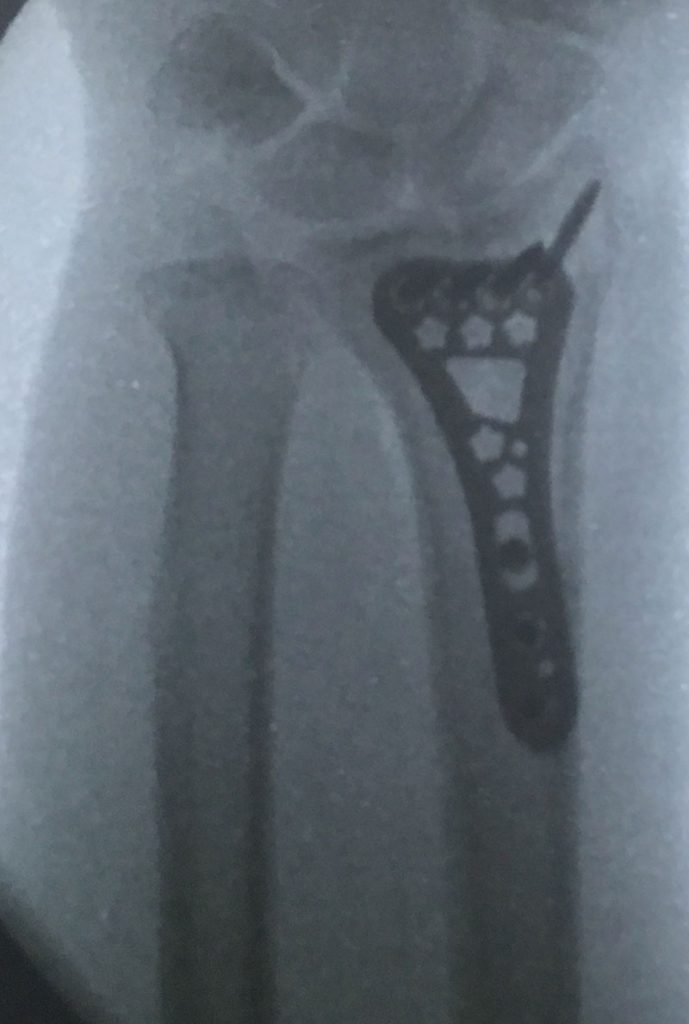

Esta radiografía del momento demostró una fractura tipo impactación de su radio dista en que la superficie articular se perdió completamente con un hundimiento central muy importante, si esto se dejara así el desarrollo de artrosis de esta articulación a corto plazo seria muy importante dejando una muñeca muy dolorosa casi para cualquier actividad, así que nos obliga a realizar una resolución quirúrgica.

Tras la cirugia en que redujimos la fractura y fijamos los fragmentos con una placa y tornillos podemos ver la restauración de la superficie articular mejorando enormemente el futuro desarrollo de esa articulación con una disminución muy importante del riesgo de artrosis temprana.